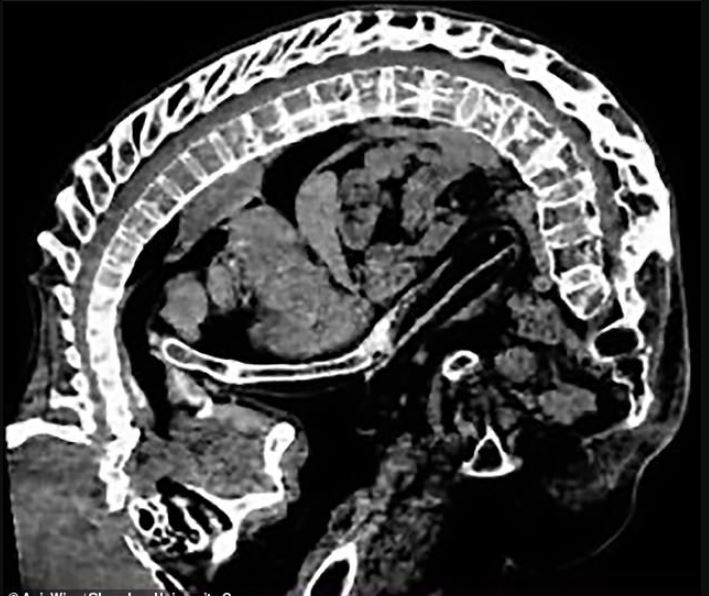

Inflamacioni në shtyllën kurrizore e bën shpinën, kafazin e kraharorit dhe qafën të ngurtësuar dhe të dhimbshëm. Inflamacioni shkakton konsumimin e kockave dhe si përgjigje, trupi prodhon kalcium shtesë për të rritur më shumë kocka, ndonjëherë në vendet e gabuara. Ky proces çon në formimin e mëtejshëm të kockave dhe kockat individuale të shtyllës kurrizore mund të bashkohen së bashku. Në raste të rënda kjo mund ta bëjë shtyllën kurrizore të përkulet më shumë përpara.

Ky lloj lakimi i shtyllës kurrizore, i cili duket si një qëndrim i përkulur përpara, quhet kifozë. Sindroma prek rreth 1.6 milionë njerëz në SHBA. Spondiloartriti aksial, një term ombrellë nën të cilin përfshihet A.S, prek një në 200 të rritur në Mbretërinë e Bashkuar.